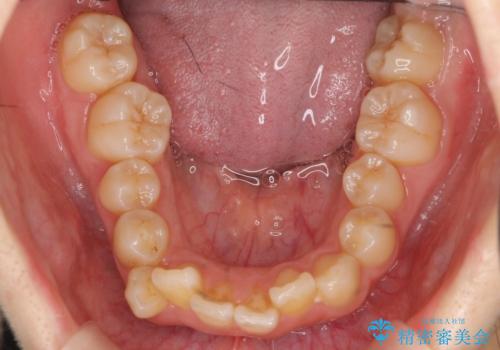

- 歯のがたつきを主訴に来院。

左右とも奥歯のがたつきがあり、左奥はすれ違っていました。

下の前歯を一本抜歯しています。(抜歯の本数は最小限にしています。)